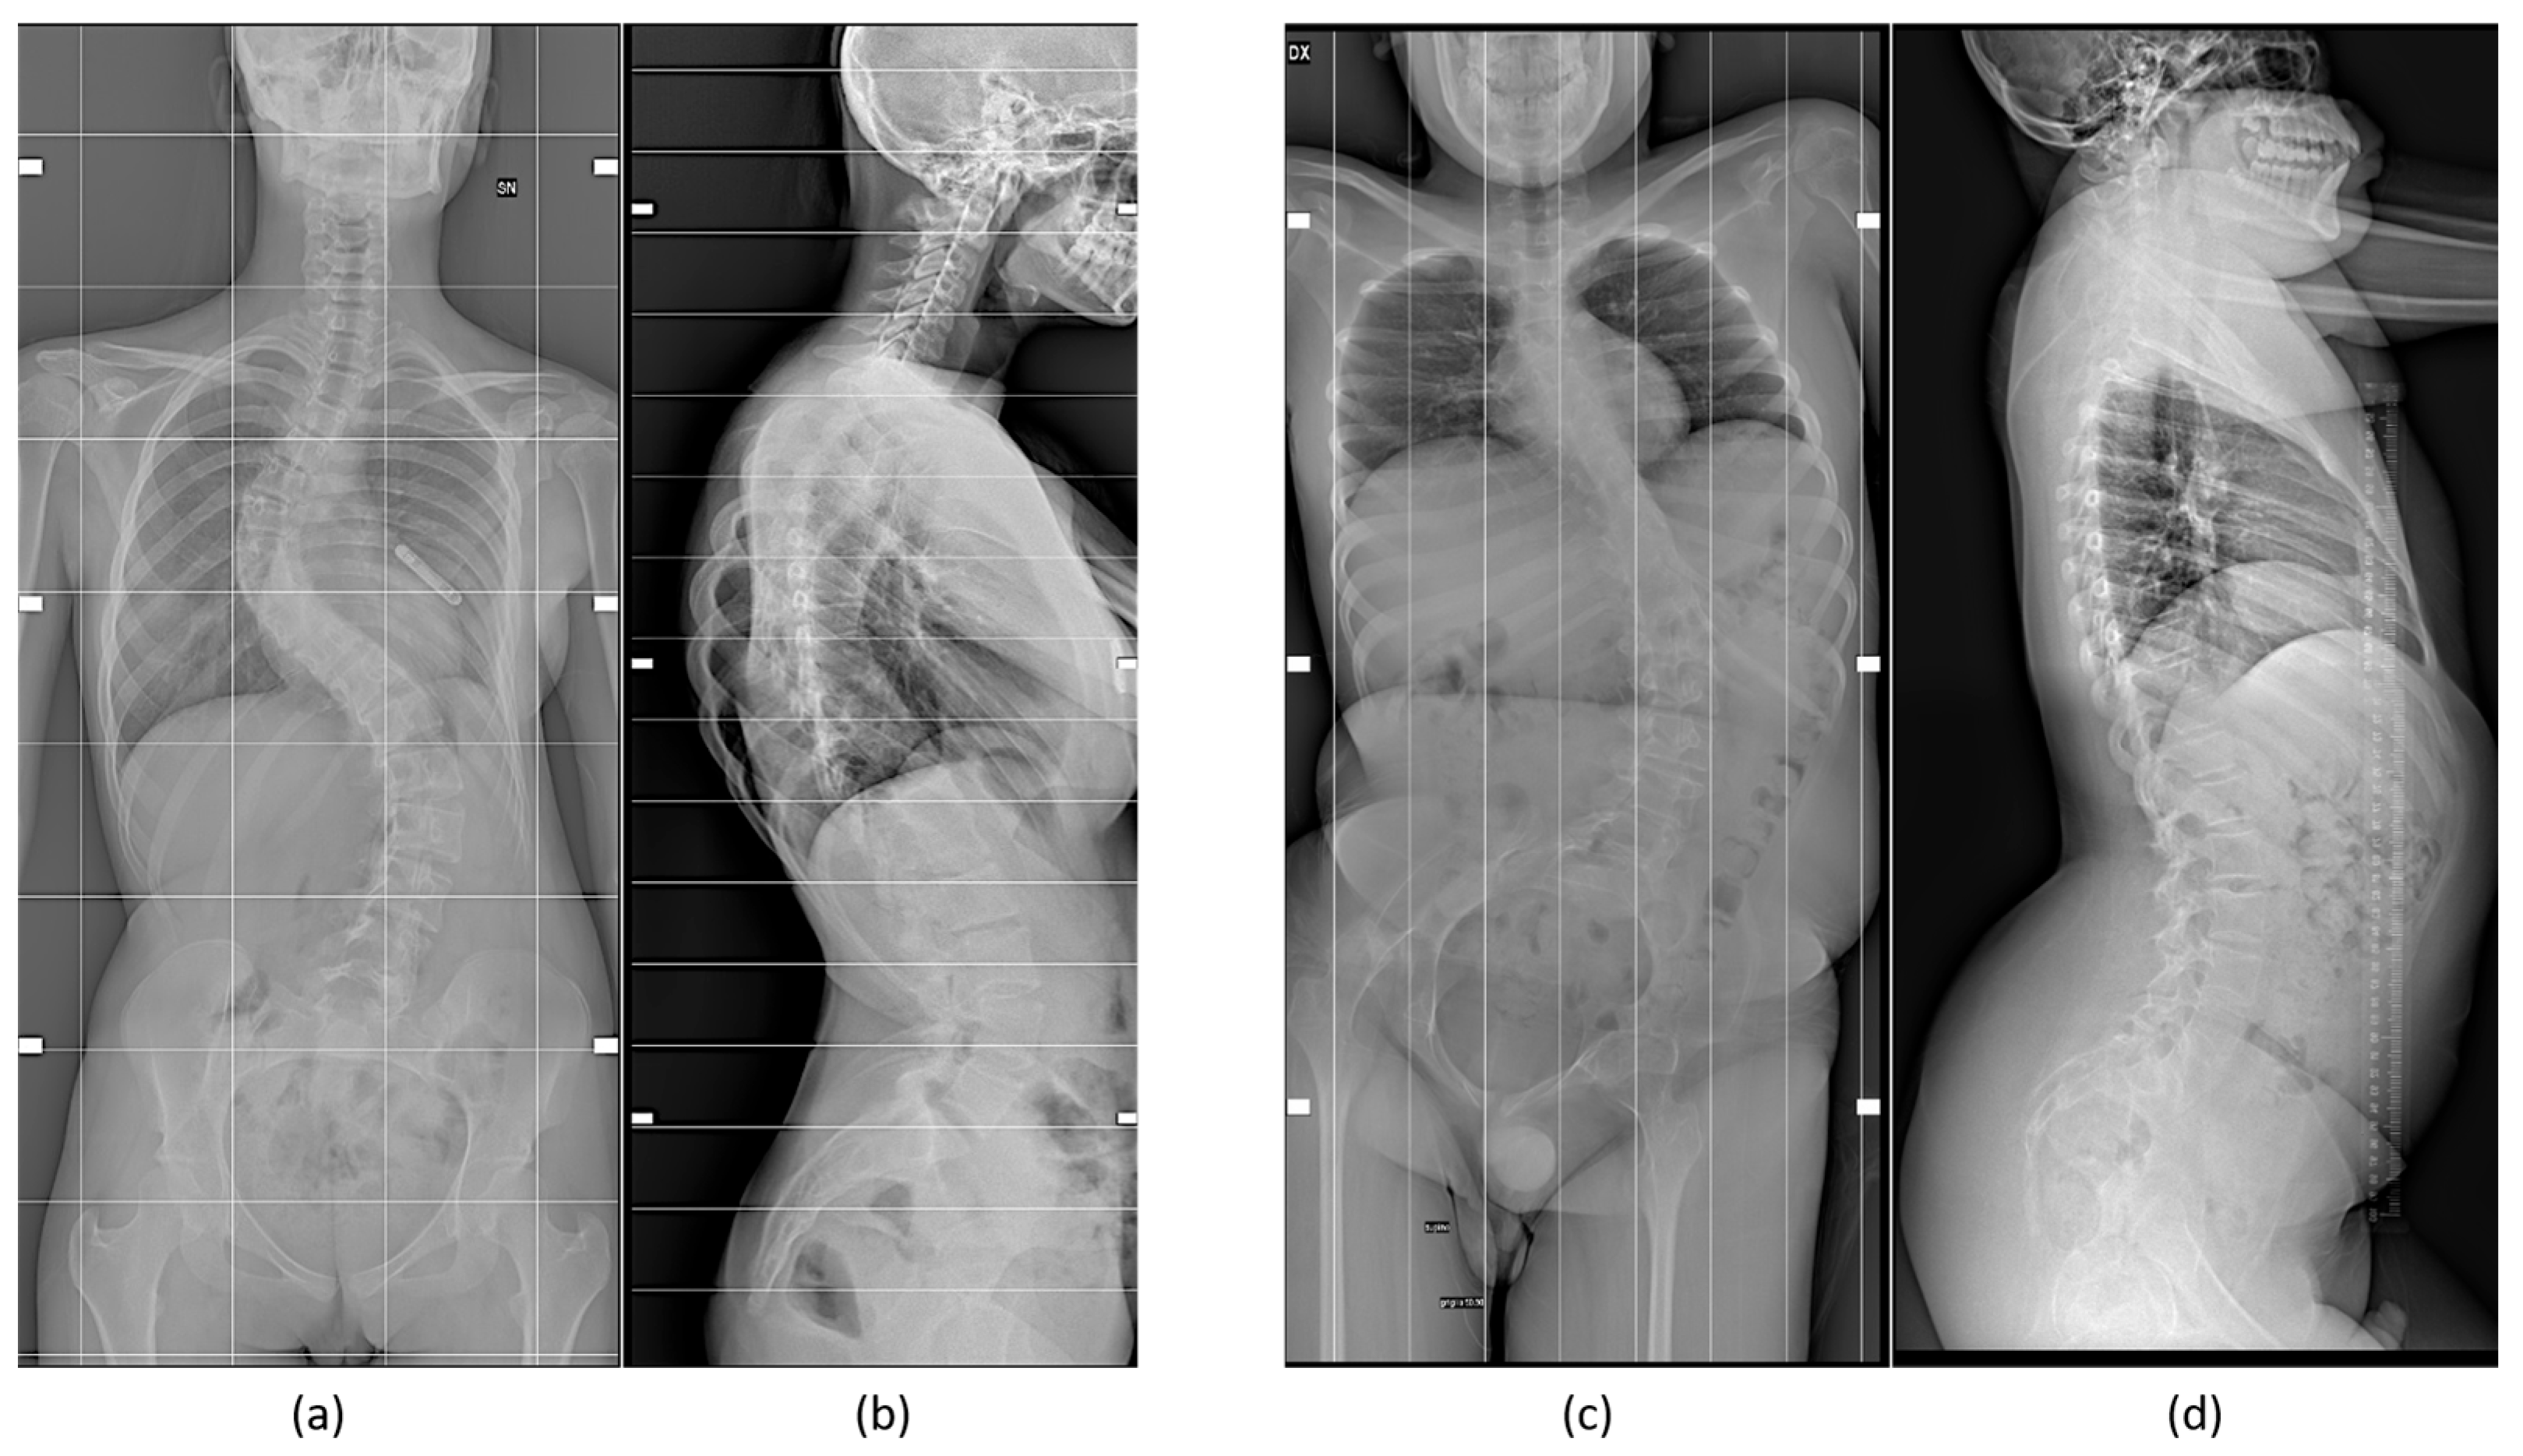

Some examples illustrating sex- and gender-specific differences include orthopedic deformities, such as adolescent idiopathic scoliosis (Figure 1), a condition that causes a curvature of the spine, typically arising during adolescence, and has an overall prevalence rate of 0.47–5.2%, occurring twice as frequently in females as in males [24,25], even if spine deformities are more severe in male subjects, as found in a retrospective study of 798 surgical patients, 140 boys and 658 girls, conducted in China [26].

Adolescent idiopathic scoliosis, a complex phenotype resulting from the interaction of different variables, related to spine anatomy and morphology [27], stiffness, growth velocity and curve patterns, and hormones, represents “one of the orthopedic disorders in which clinical evidence of sexual dimorphism is most marked” [25]. It is diagnosed around age 11–14 and 12–15 years in girls and boys, respectively [25].

Adult degenerative scoliosis exhibits sex- and gender-specific differences too, with the rigidness of spines being higher in males than in females and more pronounced in right than in left scoliosis, but only in male individuals [29]. However, another study [30] found that, while low back pain was more pronounced in male patients, scoliosis was more severe in females.